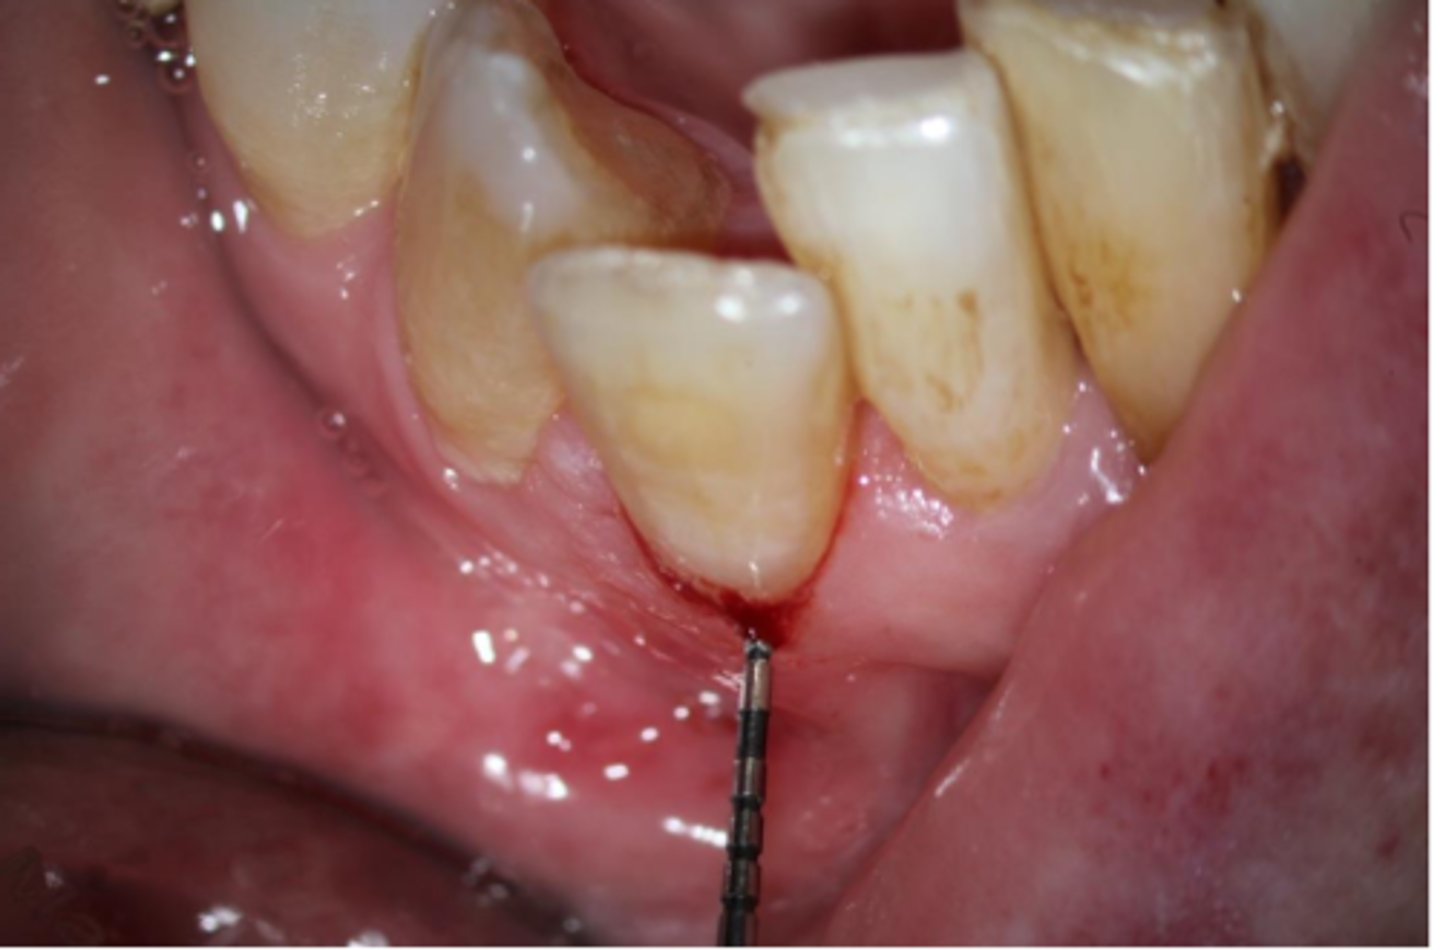

External cervical resorption (Invasive Cervical Resorption)

ID the type of resorption:

- Often asymptomatic until late stages, and may be misdiagnosed as caries

- Possible pink spot in the cervical aspect of the tooth, near gingival margin

- Often hemorrhagic on probing

- Feels hard and scratchy when probed (unlike subgingival caries which feels sticky)

A patient presents asymptomatic with a pink spot in the cervical aspect of the tooth, near the gingival margin. Upon probing, the pocket is hemorrhagic and feels hard/scratchy. What is the most likely diagnosis?

- Usually an incidental radiographic finding, especially for less advanced lesions

- Variable appearances; may be a well-defined or irregular radiolucency around the cervical aspect of the tooth

- A portal of entry is always present in the cervical region of the tooth

- The chamber/canal outline is often visible as the innermost layer of predentin around the chamber is not resorbed

Patient presents with these radiographic findings, what type of resorption?

- Incidental finding

- Radiolucency around cervical aspect of tooth

- Portal of entry present in cervical region

- Chamber/canal outline is visible

External surgical repair only

These are a part of which treatment for External Cervical Resorption (ECR)?

For lesions that are accessible through raising a flap and that are unlikely to have pulpal involvement after removal

- Raise a flap

- Complete debridement of the resorptive lesion

- Tx with 90% trichloroacetic acid (TCA) or 5.25% NaOCl

- Restoration of defect with resin-modified glass ionomer (Geristore) or Biodentine

- Flap closure and suturing